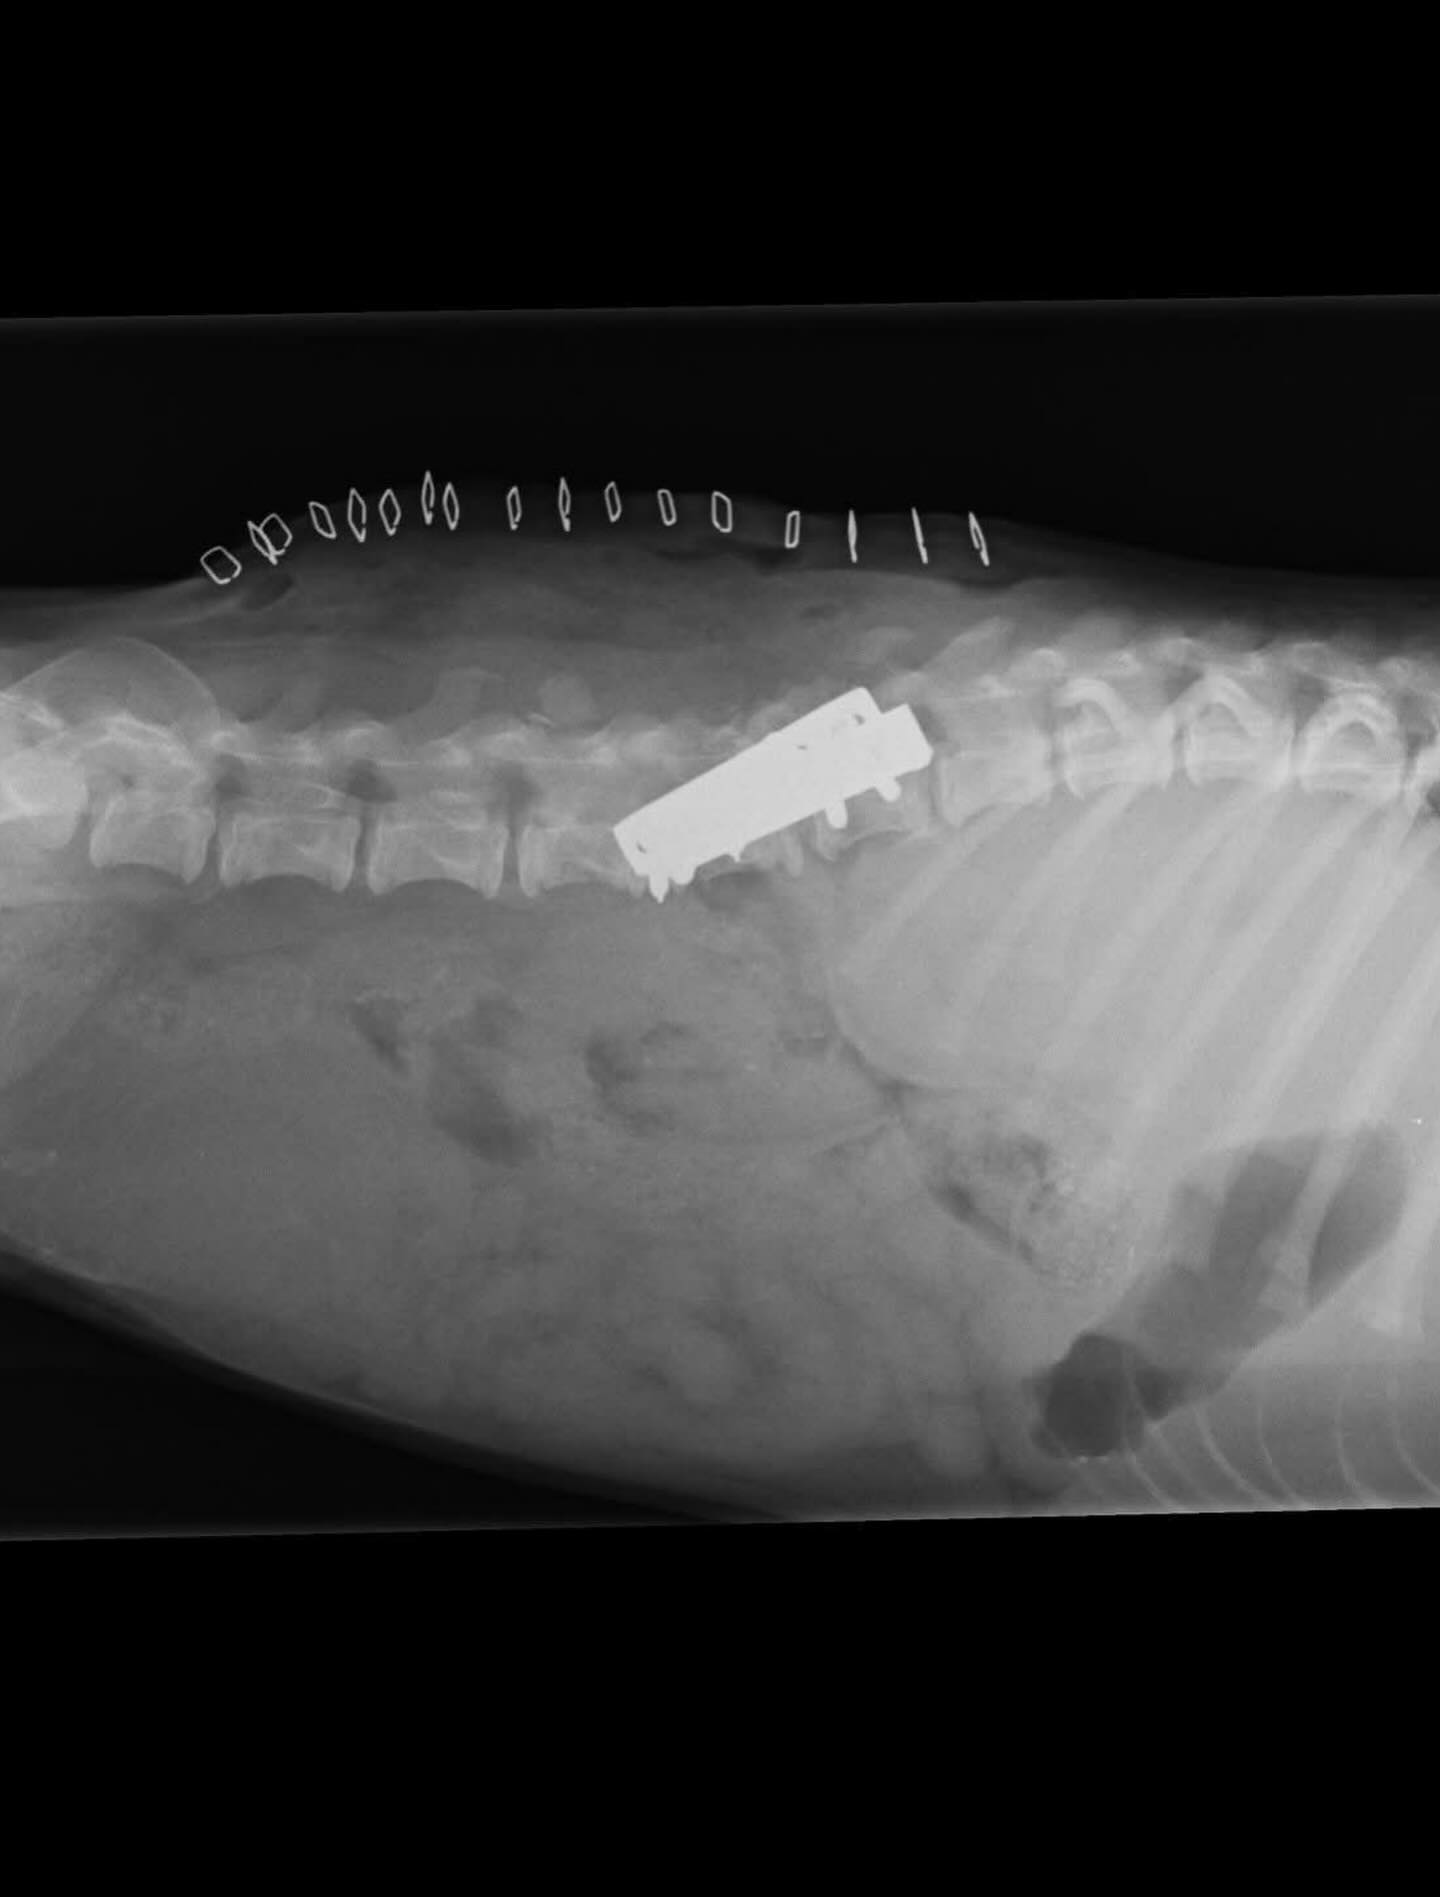

Tačiau tuo metu su kolega nusprendėme tiesiog pabandyti padaryti stebuklą. Atlikome vieną pirmųjų stuburo operacijų – nieko nežinodami, nemokėdami, bet labai tikėdami.

Viskas klostėsi sunkiai: lūžo varžtai, prasidėjo infekcija…

Tačiau mes nepasidavėme. Kovojome toliau. Stengėmės.

Viltė, kuri jau buvo ant mirties slenksčio, šiandien gyvena nuostabų gyvenimą ir juo džiaugiasi.

Ypač tada, kai matai tokius rezultatus.

Viltė perduoda linkėjimus visiems, kurie tikėjo.

Pažiūrėkite į mane – aš esu laimingas šuniukas!

Aš jaučiuosi nuostabiai.